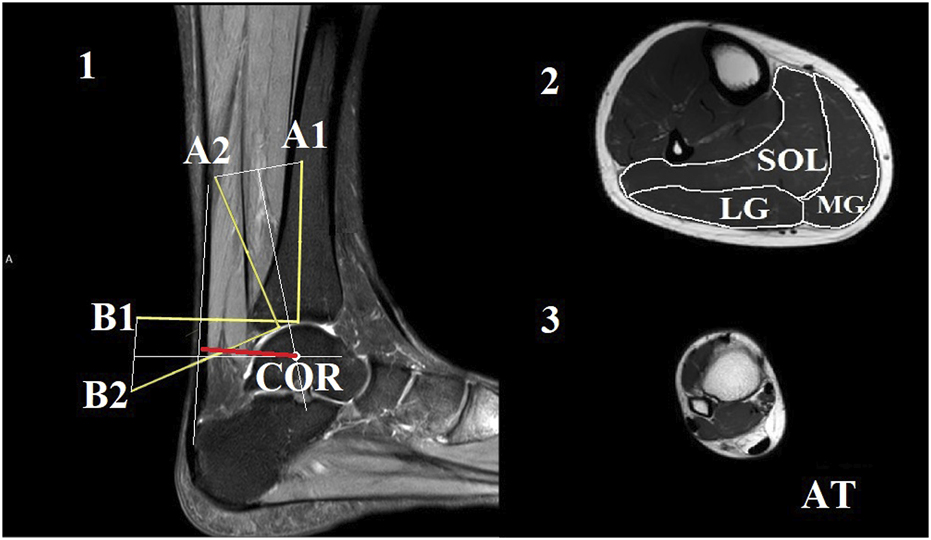

The axial plane images were analyzed using ImageJ 1.44b software (National Institutes of Health, United States). The cross-sectional area (CSA) of each muscle and the Achilles tendon was manually outlined and measured (Figure 1). To ensure the reliability of the CSA measurements, the images were analyzed by two individuals. The average CSA measured by the two analysts was used to calculate muscle volume and mass. Muscle and tendon lengths were calculated by summing the number of analyzed slices and multiplying by 0.5. The volume of each muscle was calculated by summing the volume of each slice, which is the product of the cross-sectional area and slice thickness (5 mm) (Kovács et al., 2020). Muscle mass was then calculated as the muscle volume multiplied by muscle density (1.056 g/cm³) (Winter 2009).

FIGURE 1

www.frontiersin.org

FIGURE 1. The Reuleaux graphical method was used to estimate the location of the center of rotation (COR) at the neutral joint position [1]. In this method, the talus was considered a fixed location, and the plantarflexion of the ankle was represented by the movement of the tibia with markers A1 and B1 to the next joint position marked with A2 and B2, respectively. Perpendicular lines were drawn to the bisectors of the connecting lines of A1-A2 and B1-B2. The intersection of these perpendicular lines marked the COR. The line of action for the Achilles tendon was marked in the image (indicated by the orange line). The length of the perpendicular line between the COR and the action line of the Achilles tendon (indicated by the red line) was considered as the length of the Achilles tendon moment arm. Representative magnetic resonance images from the middle of the lower leg were used for the calculation of cross-sectional areas [2]. The soleus (SOL), medial gastrocnemius (MG), and lateral gastrocnemius (LG) compartments were outlined manually. Additionally, a sample image of the maximal distal Achilles tendon (AT) was included [3].

2.5 Estimation of Achilles tendon moment arm length

We utilized the Reuleaux graphical analysis (König, 2015) to estimate the length of the ATMA by characterizing the ankle joint with the tibiotalar joint (Figure 1). In the first step, a line (L1) was drawn along the longitudinal axis of the tibia, starting from the most distal articular surface of the bone in the image taken at the neutral ankle joint position. Then, a point (A1) was marked 7 cm from the starting point of this line. Subsequently, a perpendicular line (L2) was drawn from the same starting point. Similarly, a point (B1) was placed 7 cm from the starting point on L2. The same process was repeated on the image taken from the ankle in a 15° plantar flexed position to determine points A2 and B2. The two images were then overlapped in such a way that the two talus bones aligned as closely as possible with each other. Points A1 and A2, as well as points B1 and B2, were connected by straight lines (La and Lb). Next, two perpendicular lines were drawn from the bisectors of La and Lb, and the intersection of these lines was marked as the center of rotation. The Achilles tendon action line was identified at the 90° ankle joint position as a straight line. The ATMA length was determined as the shortest perpendicular distance from the center of rotation to the tendon action line. Additionally, ATMA was normalized to body height due to the high inter individual variation, which ranged from 1.54 m to 1.92 m. To account for the joint dependent length characteristics of the ATMA, we estimated the dynamic ATMA length using a similar approach to that employed by Werkhoven and Piazza (2017a). We utilized experimentally measured ATMA data at different joint angles from a previous study conducted by Maganaris et al. (2000). First, we fitted a second order polynomial line to the original dataset. Next, we used this model to estimate the changes in dynamic moment arm length based on the ankle angle joint displacement data obtained from each participant in our study. To ensure compatibility with our data, the dataset was interpolated over the ankle angle joint displacement data. Finally, the estimated dynamic moment arm lengths were multiplied by a scaling factor. The scaling factor was determined as the measured ATMA length at zero degrees (ankle in a neutral position) obtained from the MRI images.